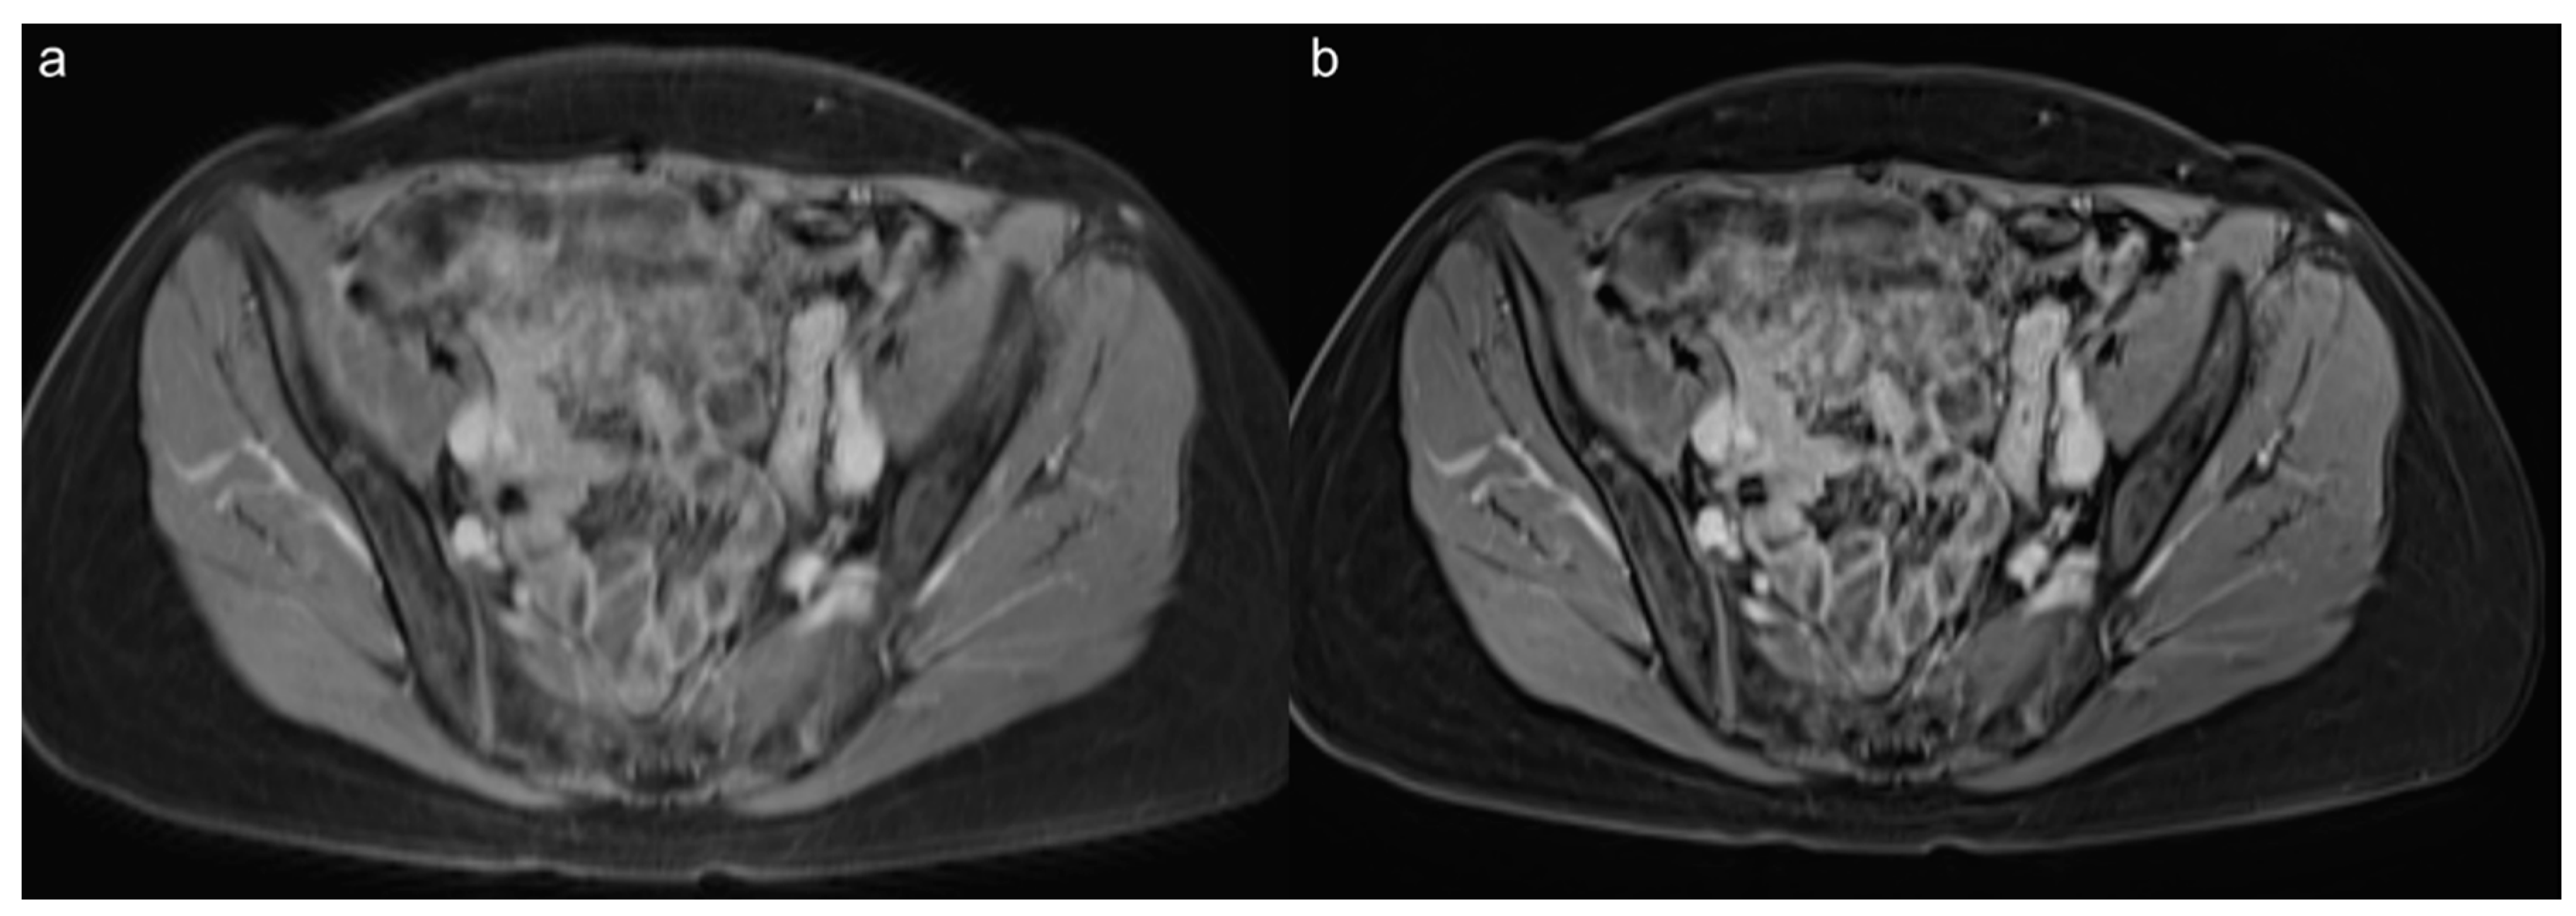

3.5. Lesion Assessment

3.6. Acquisition Time